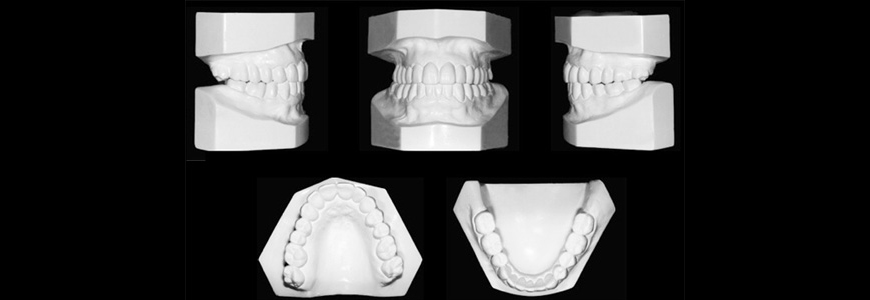

La importante necesidad de evaluar y revisar algunas radiografías de cara y cráneo, analizar una serie fotográfica clínica especial y analizar también unos moldes en yeso (replica de la boca del paciente en yeso), asegura un absoluto conocimiento del problema o de la serie de problemas que presente el paciente, tratando durante la terapia de corregir los problemas que más severidad se presenten en cada paciente.